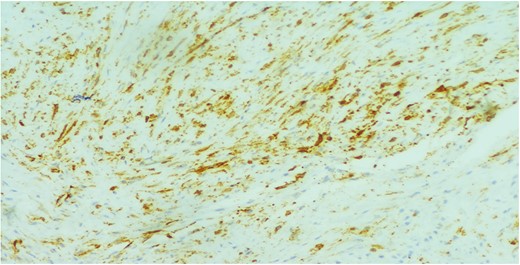

A 26-year-old female presented to our unit with recurrent right breast lump that was excised 6 years before with no available documented data. Physical examination revealed hard painless swelling occupying the medial quadrant of the right breast below the site of the old incision with no clinically palpable axillary LNs. Ultrasonography reported an ill-defined heterogeneous hypoechoic soft tissue lesion. Core needle biopsy revealed dense collagen bundles. Excision of the mass was done and paraffin sections stained by Hematoxylin and Eosin (H&E) showed benign tumoral proliferation formed of spindle cells arranged in small clustered fasicles separated by thick collagen bands (Fig. 1). Further IHE studies confirmed the diagnosis of fibromatosis supported by positive nuclear staining for B-catenin (Fig. 2). And 18 months later, she came with abdominal wall swelling, underwent CT scanning and found to be multiple soft tissue masses at the lower anterior abdominal muscles at the right lumbar and iliac regions.The largest measured ~13 × 10 cm. Core needle biopsy revealed spindle cell proliferation consistent with fibromatosis confirmed by positive reaction for SMA (Fig. 3) and B-catenin. Lesions were excised with free margins and reconstruction of the abdominal wall was carried out using a double face mesh. Final pathology report was consistent with fibromatosis confirmed by positive reaction for SMA and B-catenin.The patient had smooth postoperative course.

Spindle cell proliferation formed of bland looking cell arranged in short fascicles with dissection of breast fat lobules at the periphery (H&E, ×100x).